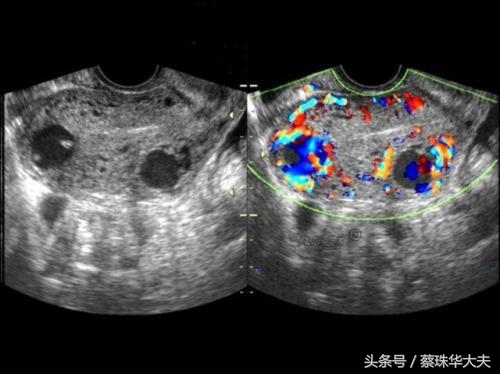

包括 卵巢肿瘤,卵巢巧克力囊肿,附件炎症性包块。

这些囊肿的特点是月经干净后复查,囊肿不会缩小,大小不变或会增大。或者B超下看上去回声乱糟糟。这些囊肿需要及时的治疗。